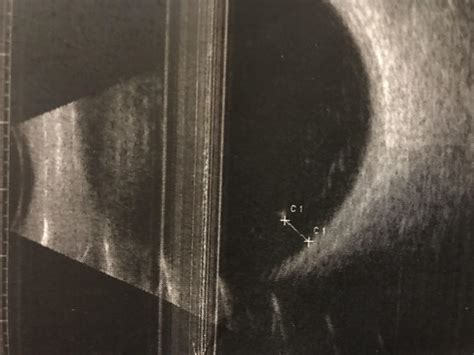

New Ultrasound Tech For Minneapolis Eye Floater Treatment Arrives

Laser Floater Treatment